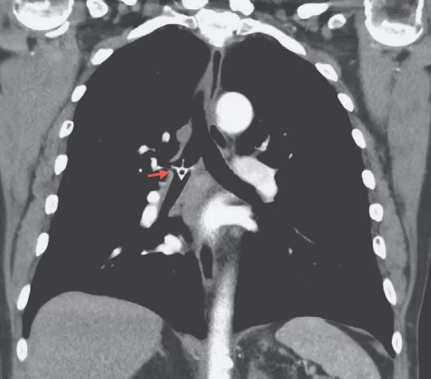

Gambar berikut ini menunjukkan tulang ayam yang bersarang di paru-paru. Seorang pria asal Australia, tersedak saat makan ayam. Setelah kejadian tersebut, ia merasa ada sesuatu yang tersangkut di tenggorokannya.

Pria tersebut melakukan pemeriksaan kedua. Kali ini doter melakukan CT scan. Mengejutkan, hasil scan menunjukkan ada tulang ayam di bagian kanan "bronchus mainstem," yaitu saluran udara yang bercabang dari trakea ke paru-paru. Bagaimana bisa tulang ayam itu tidak terdeteksi selama lima hari dan di pemeriksaan pertama kali?